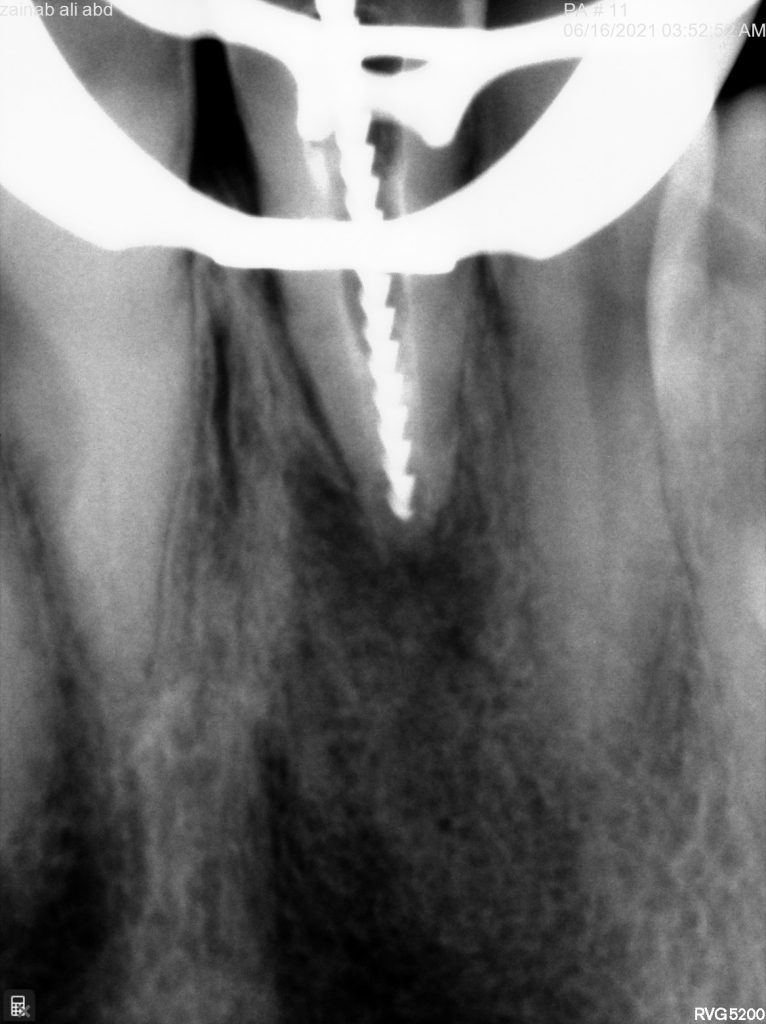

in the first visit access opening and thorough irrigation with sodium hypochloride till all the pus removed and application of non setting calcium hydroxide for one month

in the second visit the calcium removed and irrigation protocol applied as below

after dryness I applied collagen sponge to control the obturation material from escaping into the apical area

finally filled the canal with bio ceramic putty

Collagen sponge and obturation